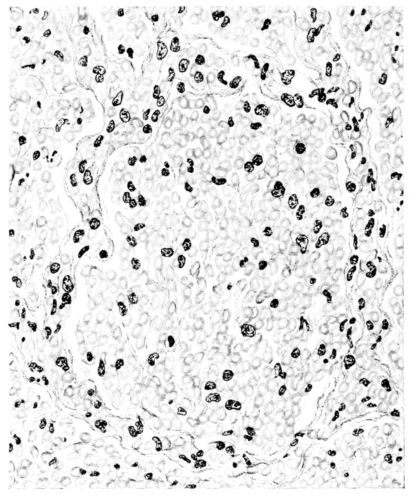

FIG. I. AUTOPSY NO. 99. ACUTE HEMORRHAGIC AND ULCERATIVE LARYNGOTRACHEITIS.

FIG. I. AUTOPSY NO. 99. ACUTE HEMORRHAGIC AND ULCERATIVE LARYNGOTRACHEITIS.

Early in the disease the congestion and the hemorrhages that have been described in the mucous membrane of the nasopharynx (14 and 94) are also conspicuous features in the lining of the trachea and bronchi (Fig. I). This membrane is swollen, turgid, red, and covered by a copious, mucous exudate which may be clear, but much more frequently is blood-stained or opaque and yellowish in color. The blood, variable in amount, may be fresh and red; and after the mucous exudate on the surface is removed, more intense red foci stand out on the congested base (47, 90, 157). Frequently, as the bronchi are approached, the red color of the mucosa becomes more intense and may have a garnet tinge. Membranes such as are encountered in the more usual necrotizing inflammatory processes, like diphtheria, have not occurred in the trachea and larger bronchi in this series (108, 128, 157).[3] The exudate peels off readily, and as indicated above, leaves a velvety red surface, 14dotted here and there with darker or more intensely red foci. Small ulcerations of the mucosa occur, but are inconspicuous (82, 156). As the finer ramifications of the bronchi are approached, the accumulation of the exudate in their lumina becomes more and more marked, and on cross section of the lung, they often stand out conspicuously on account of their increased size and projecting, seromucous, blood-stained content (101, 149, 162).